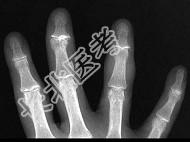

- 单项选择题女,77岁, 发现右手部肿块2周,结合图像, 最可能的诊断是 ( )

A、肌内脓肿

B、多发性腱鞘囊肿

C、骨囊肿

D、血管瘤

E、以上都不是